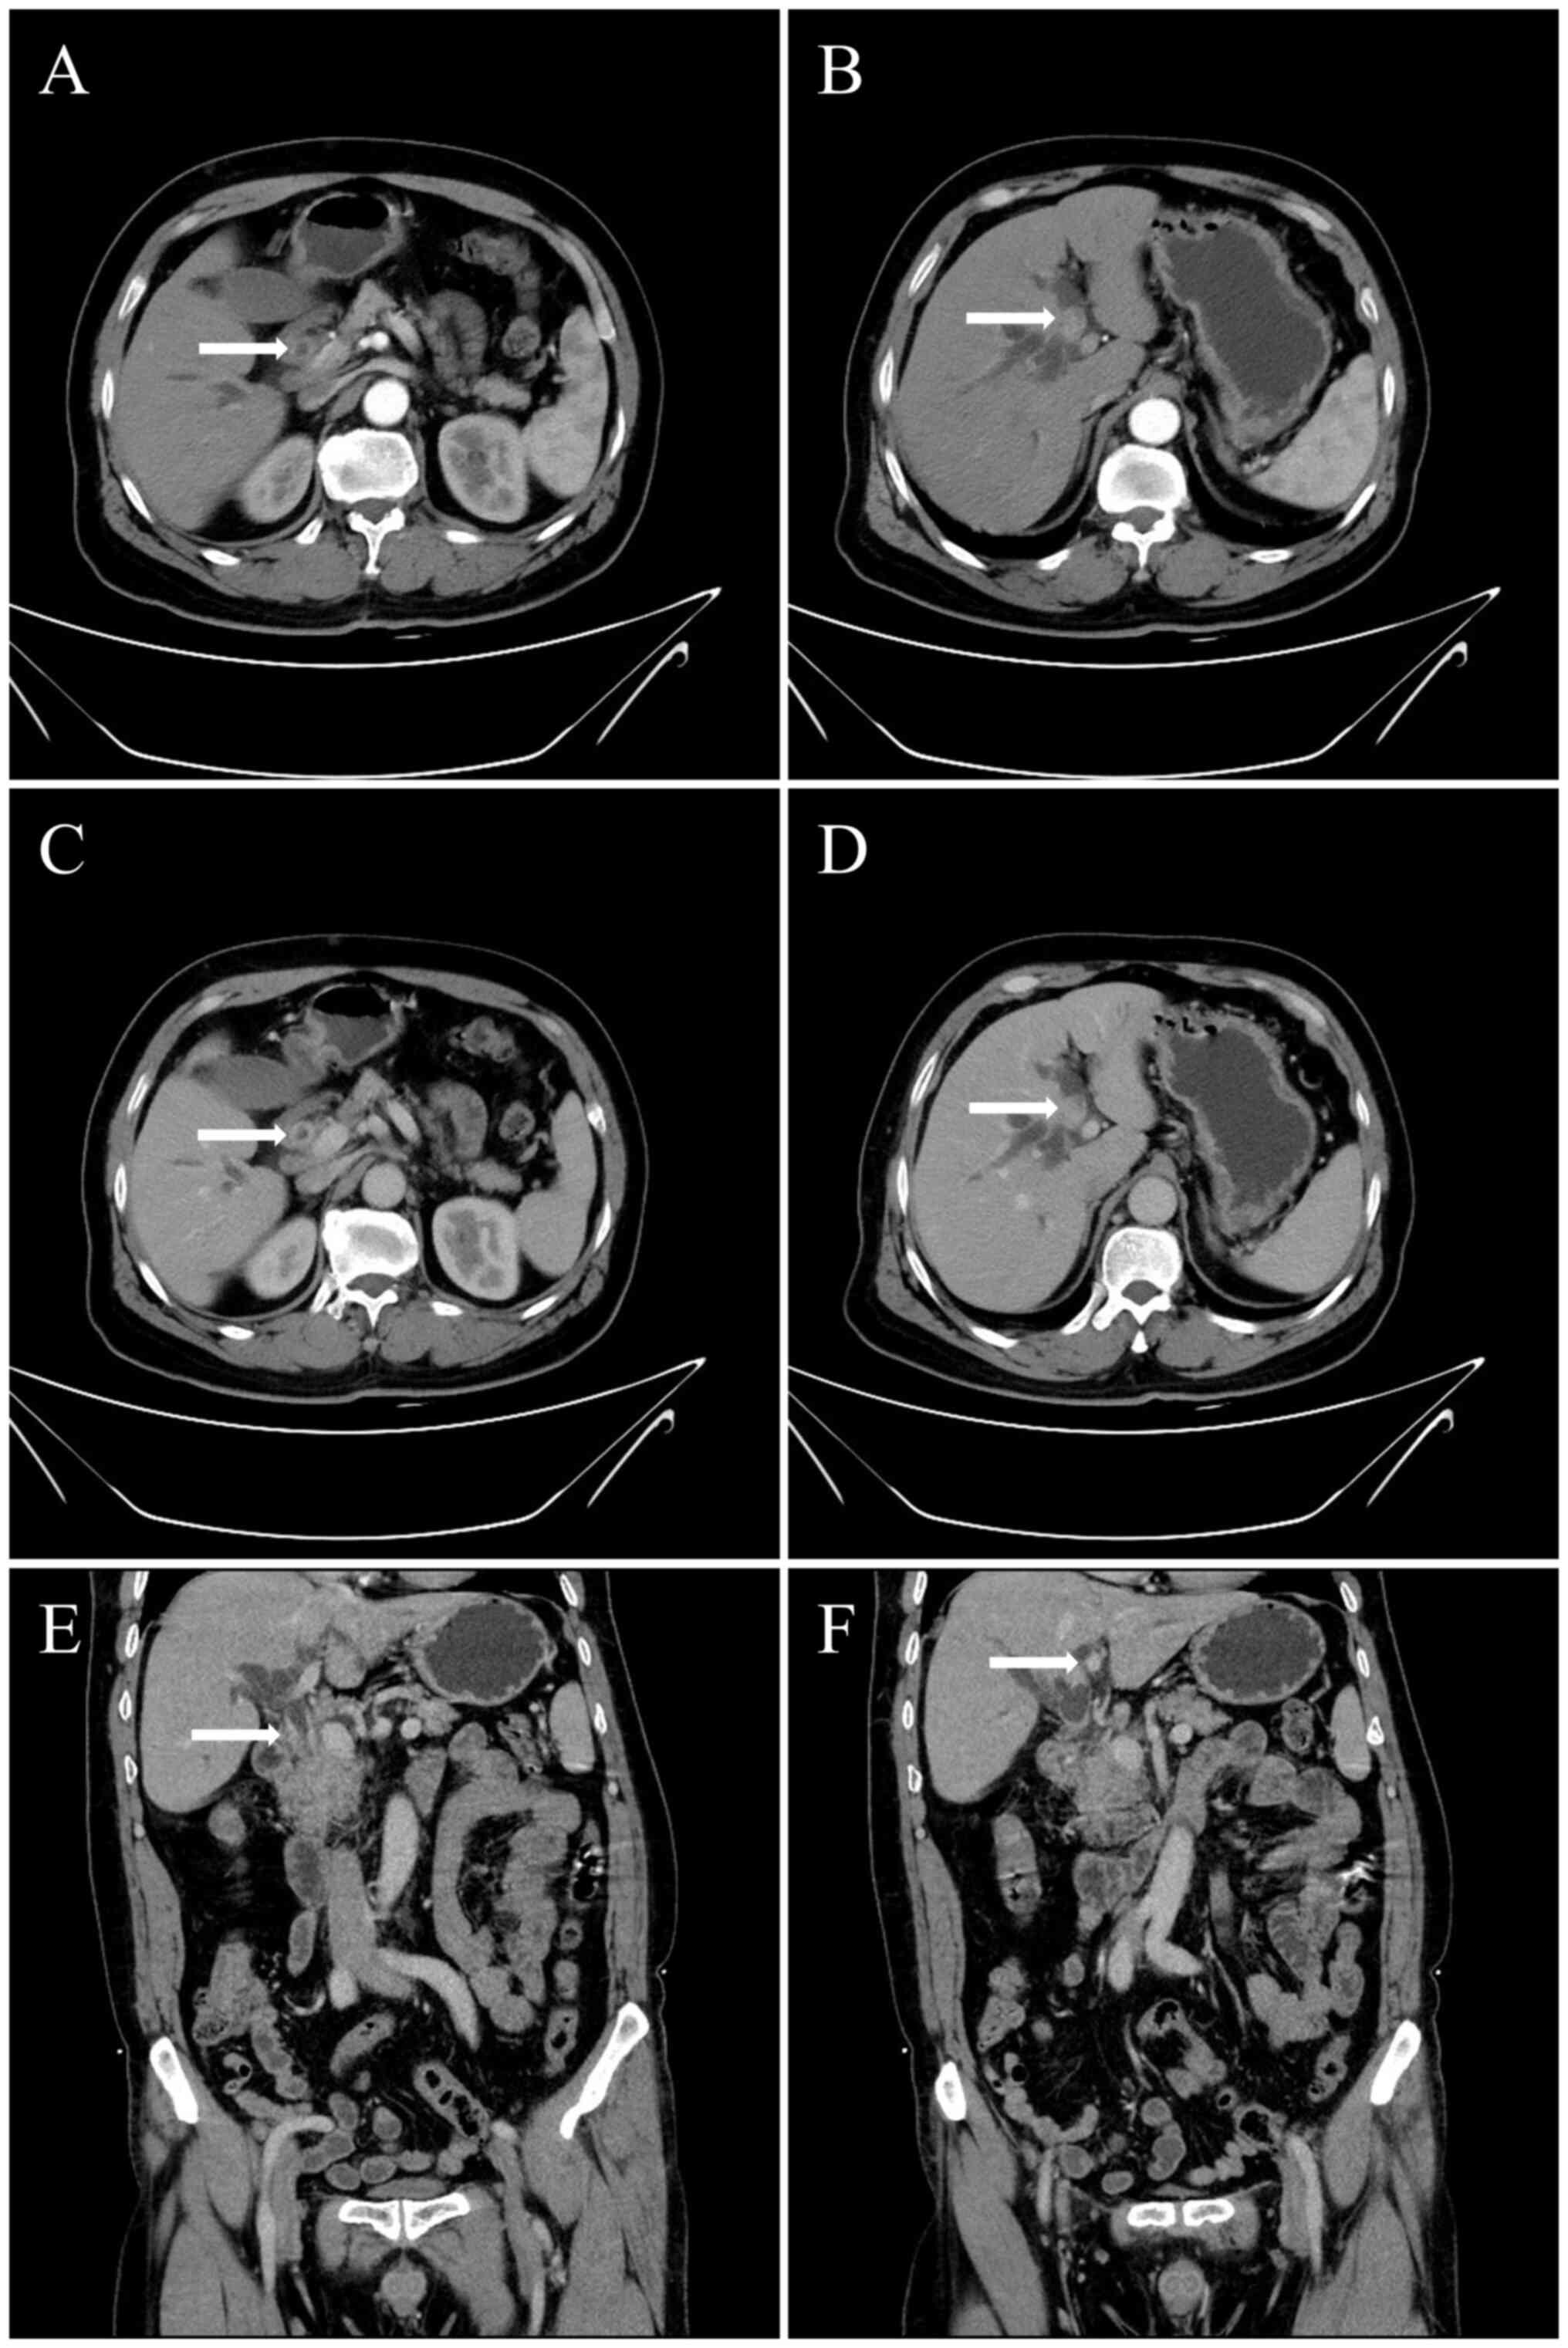

A 63-year-old male was admitted to Affiliated Jinhua Hospital, Zhejiang University School of Medicine (Jinhua, China) in October 2022 with right upper abdominal distension and pain associated with yellow sclera for 1 week. Physical examination demonstrated yellow skin and sclera. Laboratory testing demonstrated that bilirubin and transaminase levels were elevated and tumor marker testing demonstrated elevated CA199 levels (Table I). Upper abdominal enhanced computed tomography (CT; Fig. 1), enhanced magnetic resonance imaging (MRI) and magnetic resonance cholangiopancreatogram (MRCP; Fig. 2) demonstrated that the local wall of the middle and lower segments of the common bile duct were thickened, the lumen was narrow and the enhancement of common bile duct wall was visible. The intrahepatic and extrahepatic bile ducts above the stenosis were dilated, local wall of the left hepatic duct was thickened and the enhancement of left hepatic duct wall was visible. After reviewing patient medical history and imaging, the patient was diagnosed with cholangiocarcinoma arising in the left liver and in the middle and lower segment of the common bile duct. The liver function was Child B grade according to the Child-Pugh classification (7), therefore, laparoscopic left hemihepatectomy and caudate lobectomy and pancreatoduodenectomy were performed.

Figure 1.

Preoperative CT scan images. (A) CT arterial phase demonstrated moderate enhancement of the common bile duct wall. (B) CT arterial phase demonstrated moderate enhancement of the left hepatic duct wall. (C) CT venous phase demonstrated moderate enhancement of the common bile duct wall (horizontal position). (D) CT venous phase demonstrated moderate enhancement of the left hepatic duct wall (horizontal position). (E) CT venous phase demonstrated moderate enhancement of the common bile duct wall (coronal position). (F) CT venous phase demonstrated moderate enhancement of the left hepatic duct wall (coronal position). White arrows indicate location of the lesion.